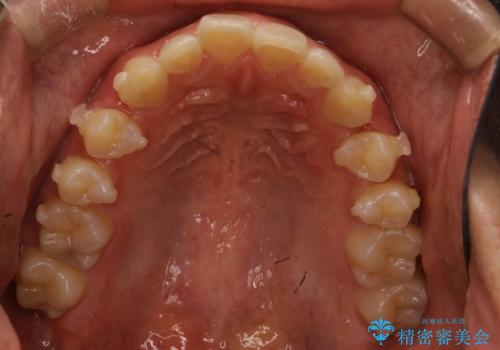

- 出っ歯を主訴に来院されました。

上の歯が全体的に下の歯の位置に比べると前方に位置しており、上の前歯が前方に傾斜している状態でした。

上の奥歯を後方に移動して、隙間を作り、前歯を引っ込める計画としました。